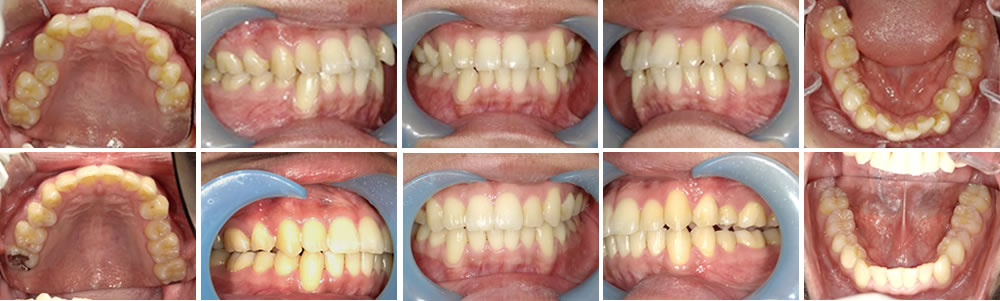

マウスピース矯正(インビザライン)で前歯の叢生を改善した症例

年齢

30代

性別

男性

症例を見る